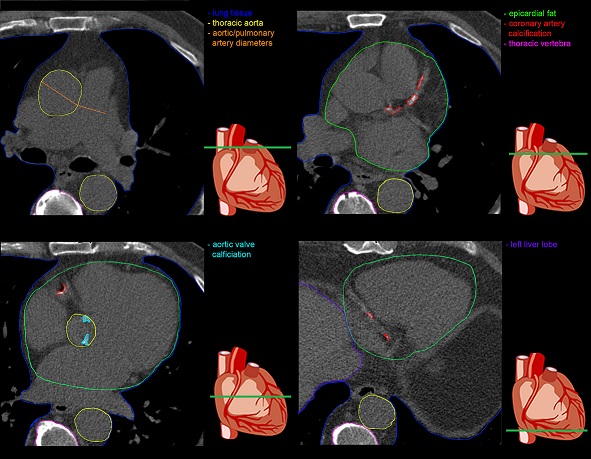

This paper shows that we can extract a lot of information from plain cardiac CT. While calcium scoring is an obvious result, it is also possible to learn the amount of epicardial fat, an increasingly recognized prognostic factor of cardiac events, appearance of lungs, pulmonary arteries, breast and also extra thoracic information like liver fat.

• Cardio-metabolic and general health markers may be derived without changes to the scan protocol.

• Those include epicardial fat, aortic valve calcifications, liver fat, bone density, and lung density.